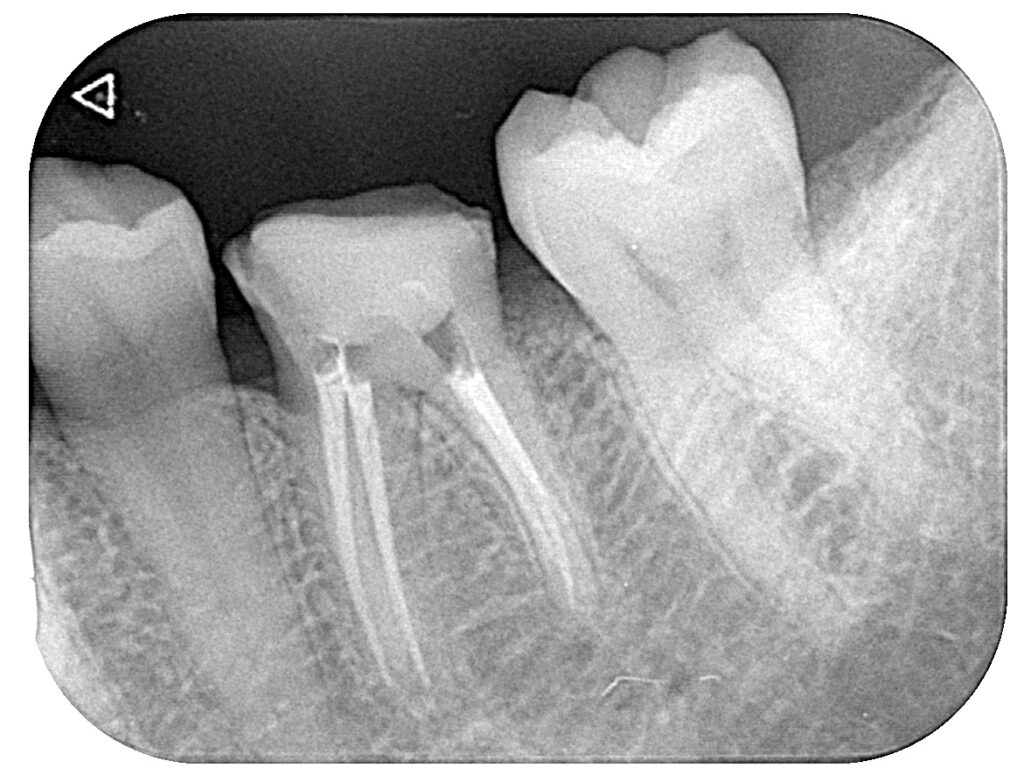

根の状態に問題がないことを確認し、

根管内に薬を詰める処置(根管充填)を行いました

(※根管充填後のレントゲンです)